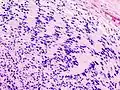

Illustrations

Neurinome subcutané_Antoni_B.jpg)

_Antoni_B.jpg)